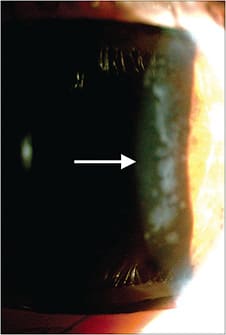

Centration of the treatment zone is the most crucial factor for success with ortho-k. Lenses that decenter cause various problems that can be observed both with corneal topography and on the ocular surface once the lens is removed. Common visual concerns that arise from a decentered lens include a non-uniform treatment zone that causes insufficient vision correction upon lens removal, early regression toward a more myopic refractive error before the day ends, and distortion in quality of vision from induced irregular astigmatism. Besides visual complaints, the ocular surface can also show insult from a decentered lens, such as positive epithelial staining on the corneal and conjunctival tissue or stromal edema (Figure 1). A decentered lens may also not generate sufficient peripheral defocus within the central pupil and therefore fail to offer efficacious myopia management.